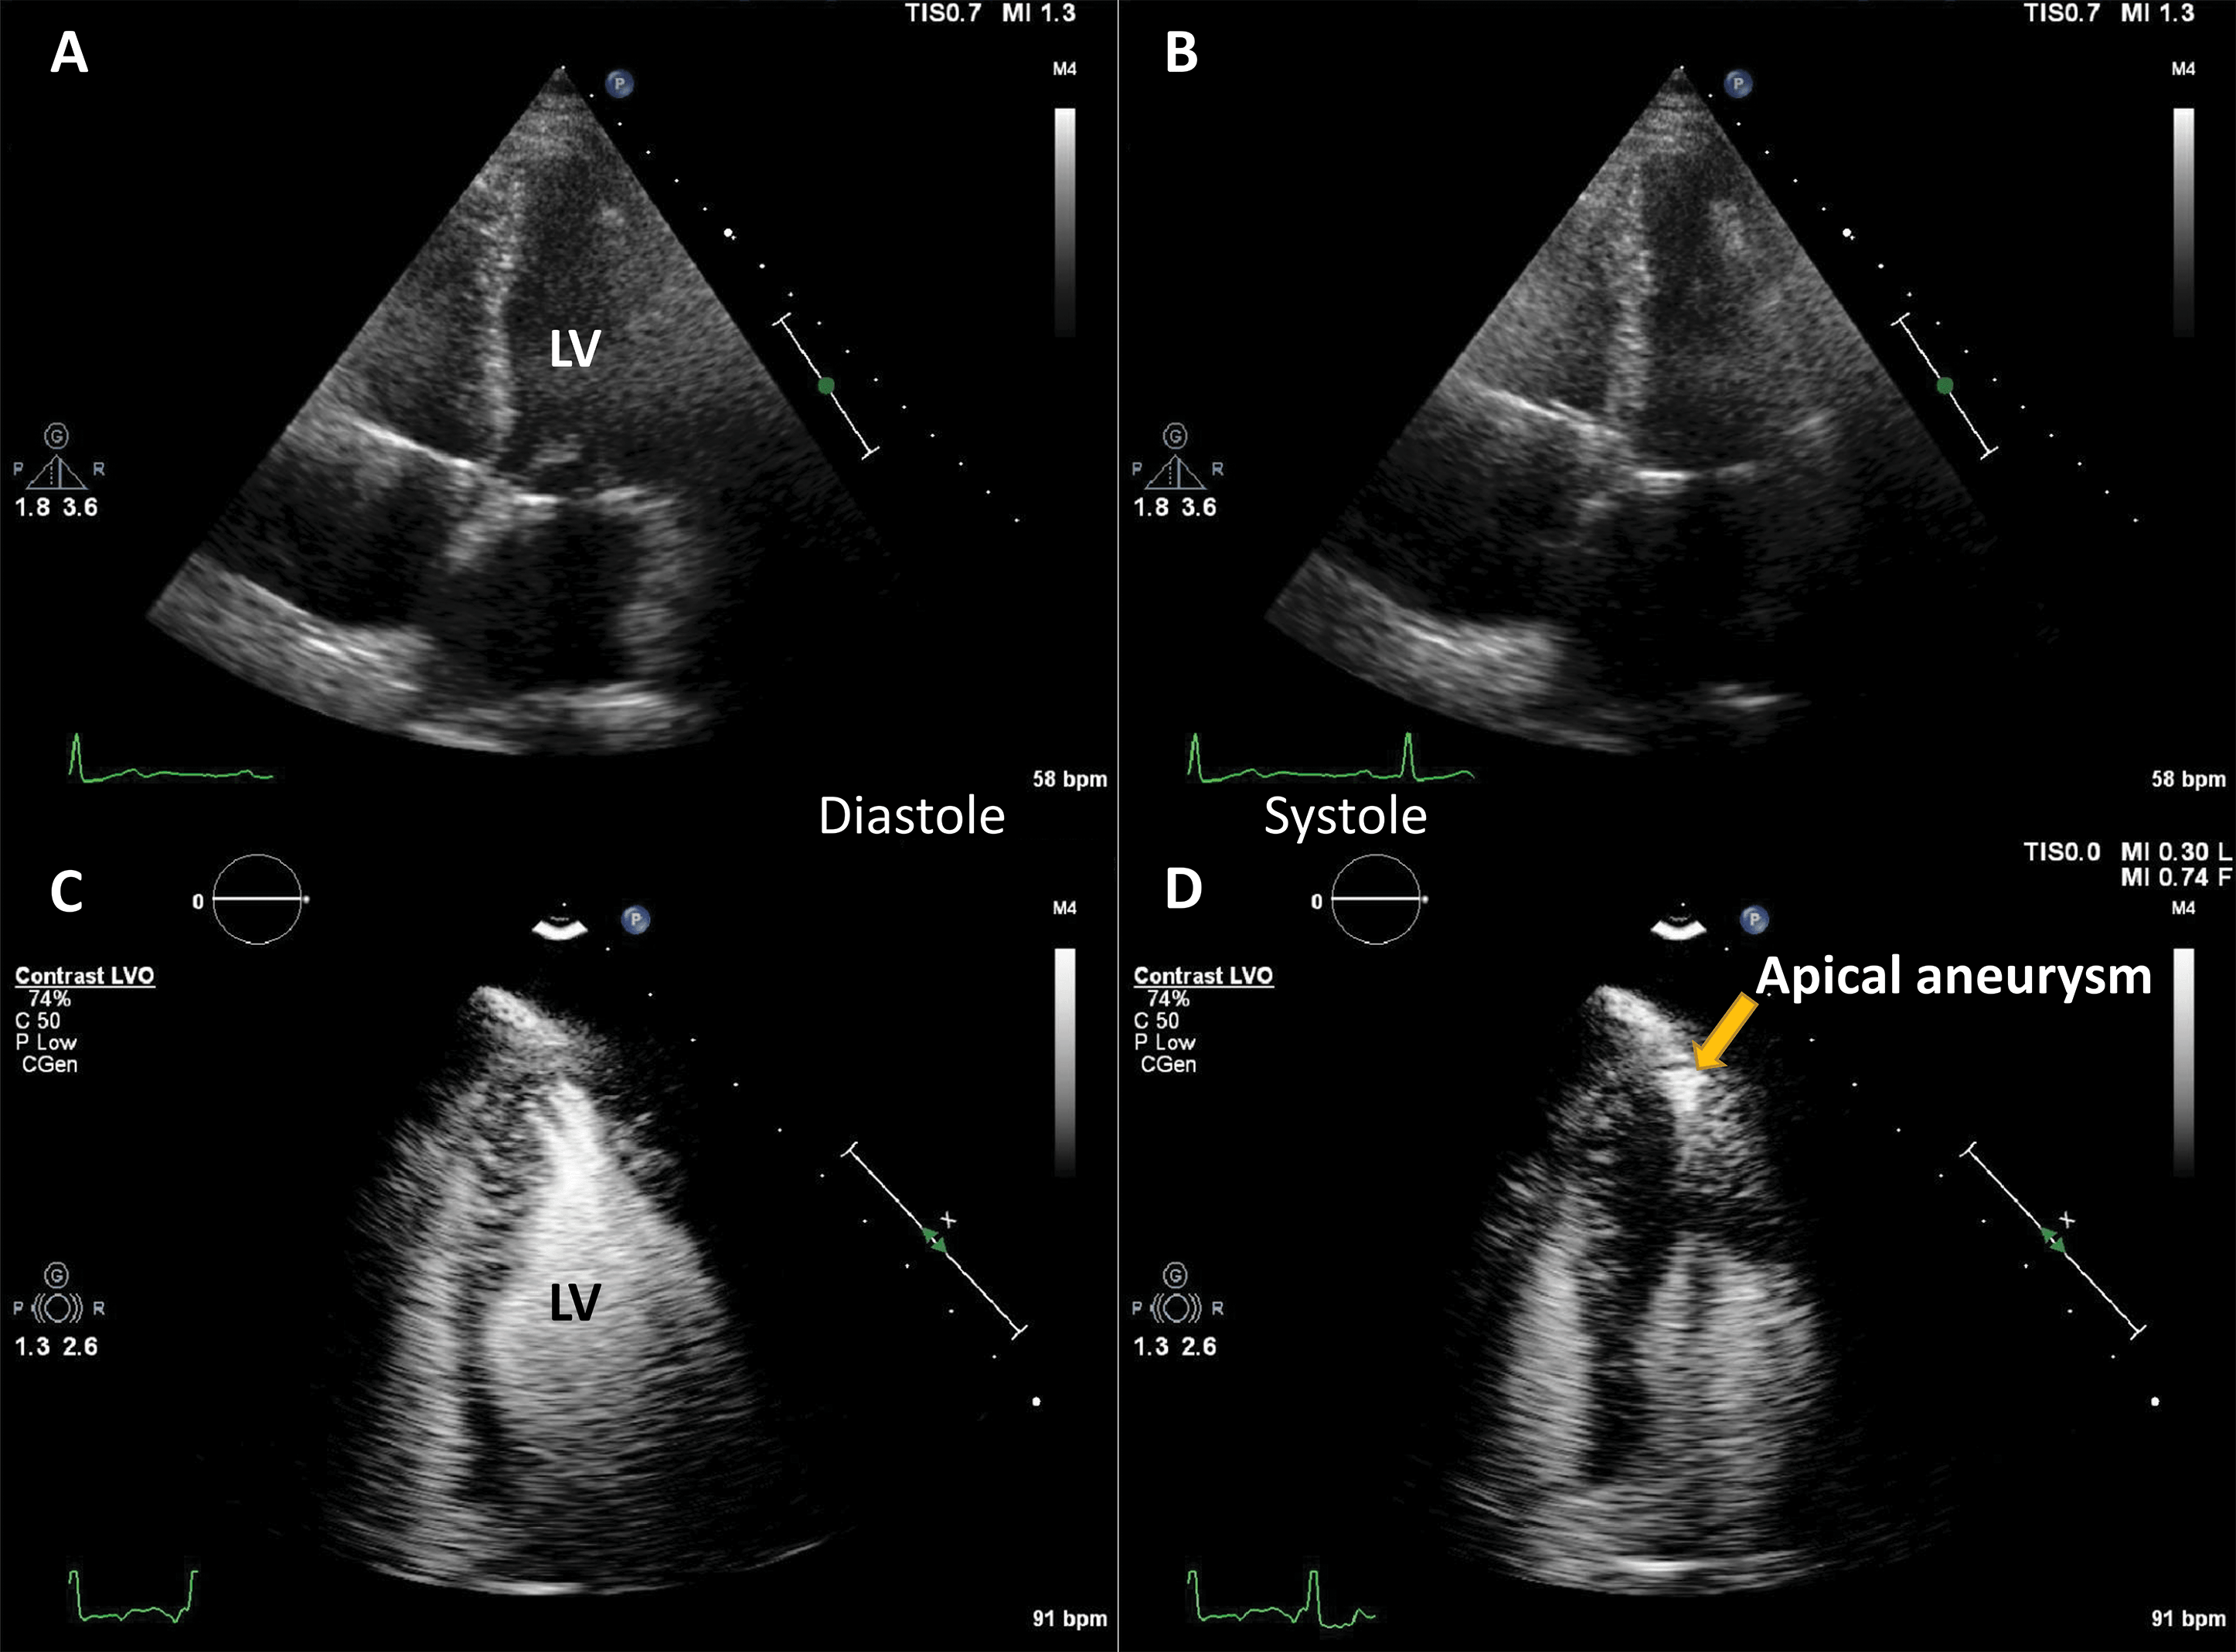

The largest body of evidence for MEE concerns the indication for LVO for enhancing the endocardial borders [10, 11, 12, 13, 14, 15]. This is achieved by using repetitive intravenous boluses of UEA, and sometimes continuous low-dose infusion. Guidelines indicate the use of LVO to enhance the endocardial borders in cases when the LV dimensions, function or regional wall motion cannot be accurately assessed using non-enhanced ultrasound [7, 14]. The general “rule of thumb” is to use microbubble UEA in cases where two or more contiguous myocardial segments are not properly visualized with non-enhanced ultrasound [13]. Of course, recent years have seen tremendous improvement in image quality for clinical ultrasound systems. But despite the introduction of harmonic imaging as a standard, some images remain non-diagnostic (Fig. 2). Moreover, harmonic imaging represented a significant leap in MEE [16, 17], leading to the present-day contrast-specific imaging modalities.

Fig. 2.Left ventricular opacification (LVO) for endocardial border delineation. Example of baseline non-enhanced echocardiography images in apical 4-chambers (A) and apical 2-chambers (B) views, where the visualization of the endocardium is suboptimal over several segments. After intravenous injection of a bolus of UEA, there is full opacification of the LV cavity, with clear delineation of the endocardium in all segments (C, D). Source: personal collection.